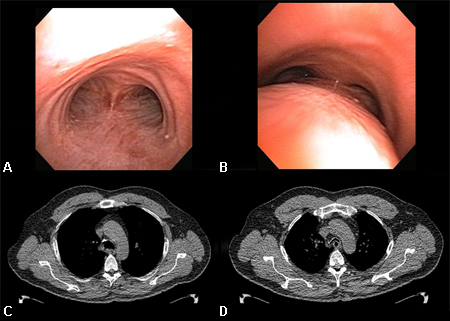

Dynamic airway collapse: A. bronchoscopic view on inhalation; B. bronchoscopic view on exhalation showing dynamic airway collapse; C. CT chest showing normal airway on inhalation; D. CT chest showing significant airway collapse on exhalation

From the collections of Jose Fernando Santacruz MD, FCCP, DAABIP and Erik Folch MD, MSc; used with permission